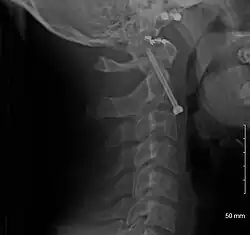

A fracture of both pedicles of the axis is termed a Hangman's fracture.

Fractures of the dens are classified into three categories according to the Anderson Alonso system:

- Type I fracture - Extends through the tip of the dens. This type is usually stable.

- Type II fracture - Extends through the base of the dens. It is the most commonly encountered fracture for this region of the axis. This type is unstable and has a high rate of non-union.

- Type III fracture - Extends through the vertebral body of the axis. This type can be stable or unstable and may require surgery.[1]

-

A fracture of the base of the dens as seen on plain X-ray -